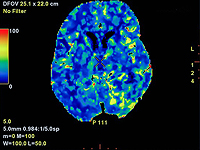

Американские ученые: алкоголь и табак ускоряют старение мозга

Регулярное употребление алкоголя и табака заставляет мозг стареть несколько быстрее. К такому результату пришли ученые, сопоставившие с помощью искусственного интеллекта снимки головного мозга с привычками людей употреблять алкоголь и табак.